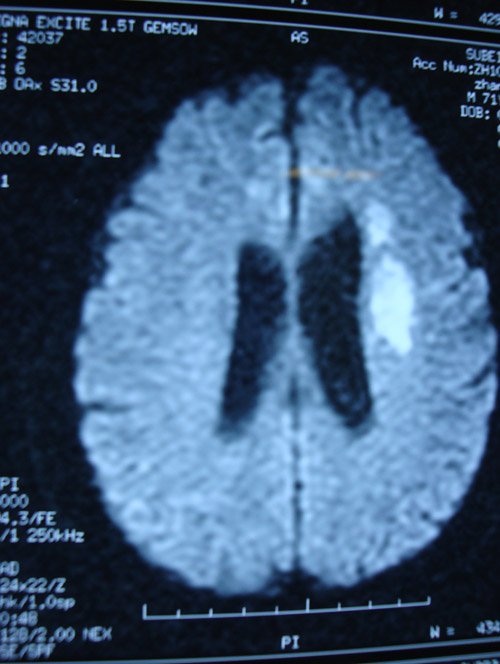

MR示:左侧放射冠区、左侧顶叶、左侧枕叶多发急性梗死;脑萎缩改变。